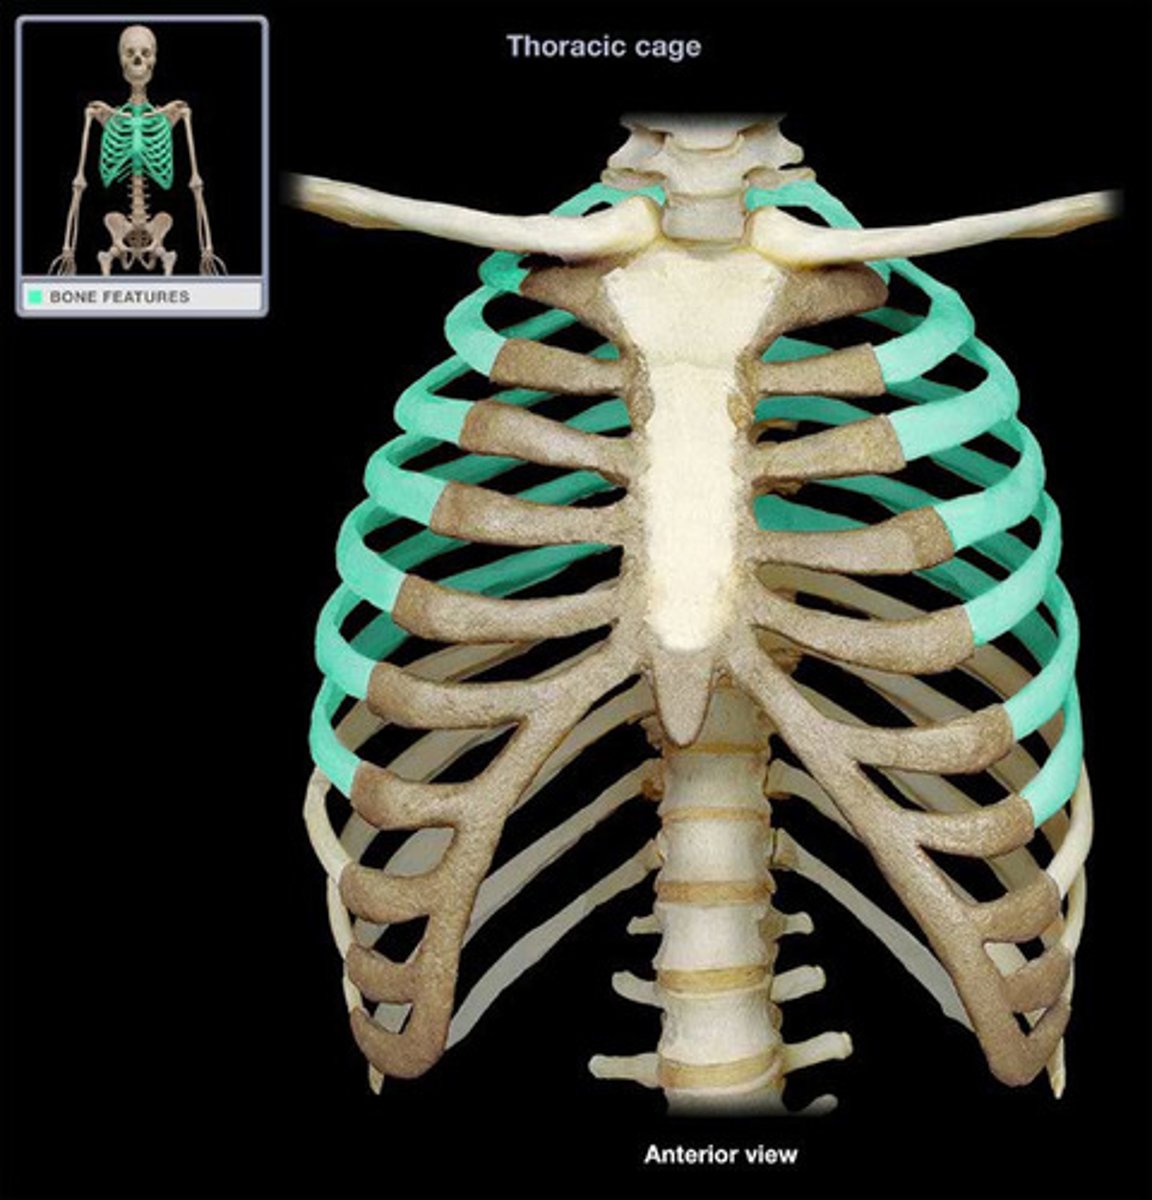

Vertebrosternal Ribs

Sternum

Manubrium

Body

Xiphoid Process